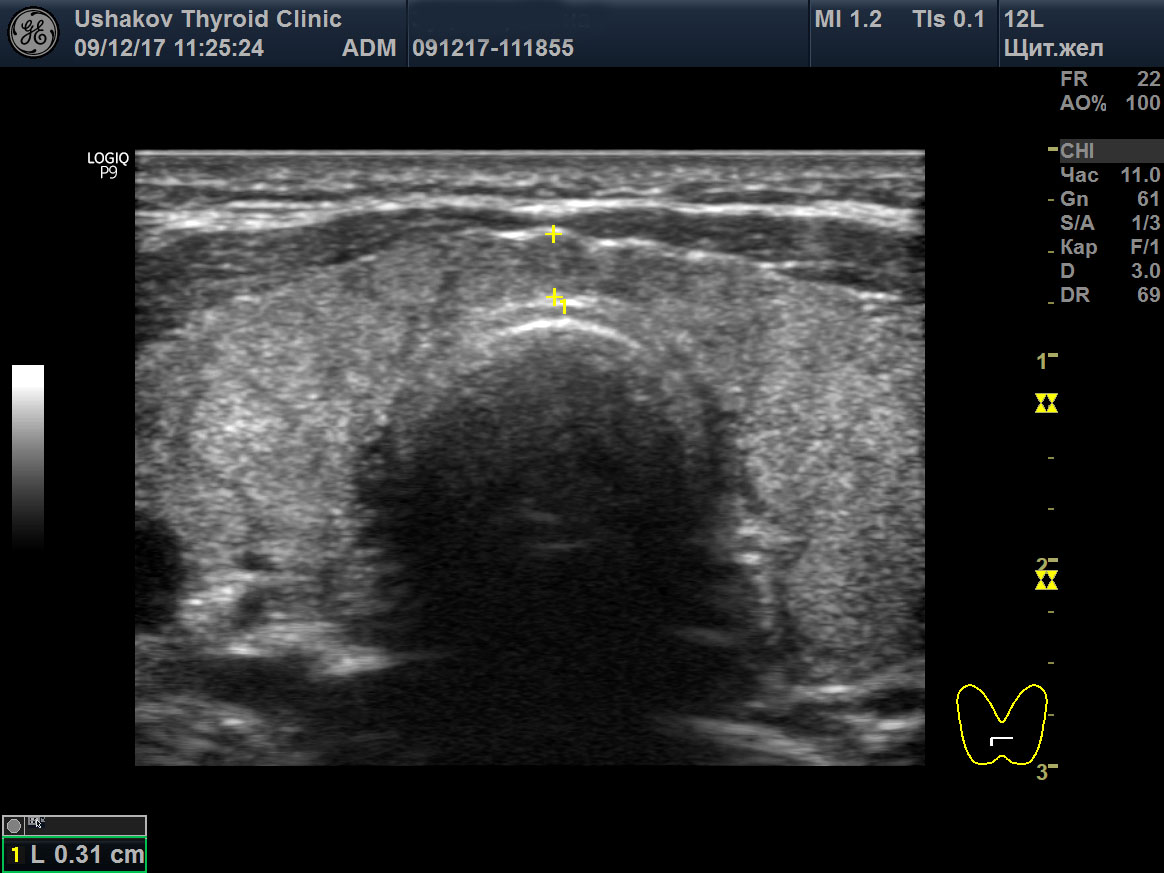

Узи щитовидной калининград

Узи щитовидной калининград 108 фотографий